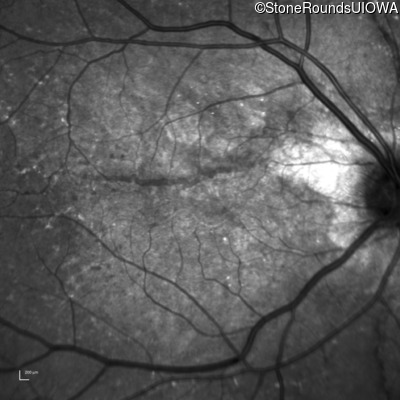

Infrared Fundus Photograph - Right - 20/25 +1

Exemplar